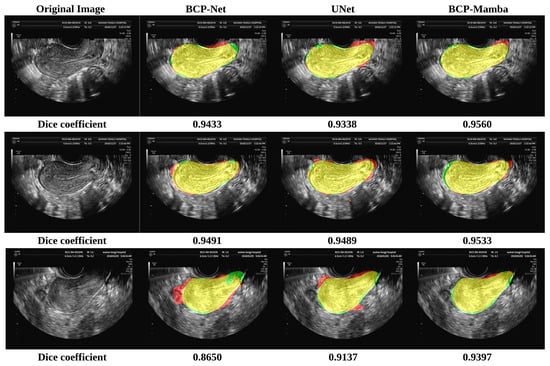

In the comparison plot of results (Figure 4), each network has three distinct sections, indicated by colors representing the ground truth (green), Predicted Results (red), and the part of overlap between the ground truth and Predicted Results (yellow). Notably, the analysis shows that the BCP-Mamba model displays the widest area of overlap between the ground truth and predicted outcomes (yellow) compared to the areas obtained with the BCP-Net and U-Net architectures. This observation suggests that the BCP-Mamba model achieves more agreement with the ground-truth annotations, indicating higher segmentation accuracy and consistency with the underlying anatomical structures in transvaginal ultrasound uterine images.

These findings are consistent with the quantitative assessment metrics discussed earlier, suggesting the improved performance of the proposed BCP-Mamba model in accurately segmenting the plasma membrane layer.

These results underscore the significant advancements achieved by leveraging semi-supervised training with unlabeled data, enhancing the model’s ability to capture complex anatomical structures and nuances present in transvaginal ultrasound uterine images. Such improvements hold promise for advancing the diagnostic accuracy and treatment planning in uterine pathology, contributing to enhanced patient care and clinical outcomes.

Our experimental results indicate that the proposed semi-supervised segmentation model significantly outperforms both the BCP-Net and U-Net models in segmentation accuracy. Specifically, the Dice coefficient, Jaccard index, ASD, and HD_95 metrics consistently show higher values for our model, with mean (SD) values of 0.8655 (0.0710), 0.7762 (0.1051), 40.04 (21.61), and 14.5 (8.9), respectively, highlighting its superior performance. The comparison chart (Figure 4) vividly illustrates this improvement, with the BCP-Mamba model showing the largest area of overlap between ground-truth and Predicted Results, represented by the yellow region, indicating a higher concordance with ground-truth annotations and enhanced segmentation precision.

Figure 4. Results of the BCP-Net, UNet, and BCP-Mamba models. Ground truth (green), Predicted Results (red), and the part of overlap between the ground truth and Predicted Results (yellow).